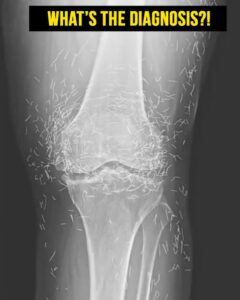

When a 65-year-old South Korean woman went in for knee pain, doctors weren’t expecting to strike gold. But that’s exactly what they found.

Acupuncture, a centuries-old alternative treatment, involves inserting needles into the body at specific points to relieve pain or treat illnesses. In this case, the needles— presumably made of gold — were intentionally left in her knees for continued stimulation.

He also warned that embedded needles can complicate X-ray readings. “The needles may obscure some of the anatomy,” Guermazi said in 2013.